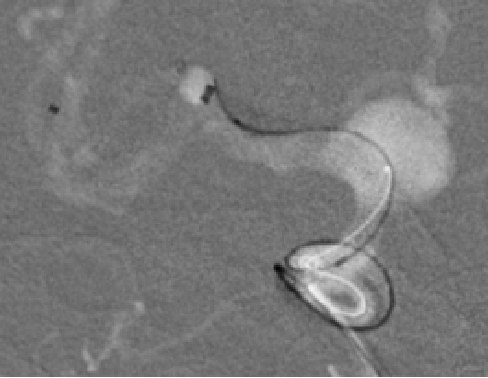

DSA

测量

5F navien对比

TJMC14测量长度

锚定过短,ped释放时掉动脉瘤内

Ped 3.5x30

木马技术:navien到达M1,ped带管到M1释放

缓慢逐段推拉打开,逐段调整最佳工作位

侧位观察ped打开不全,回收再推挤及支架外轻柔按摩打开!

造影剂明显滞留

瘤内均匀填圈:axium1440、1240、泰杰1030、930

术后次日头颅CT